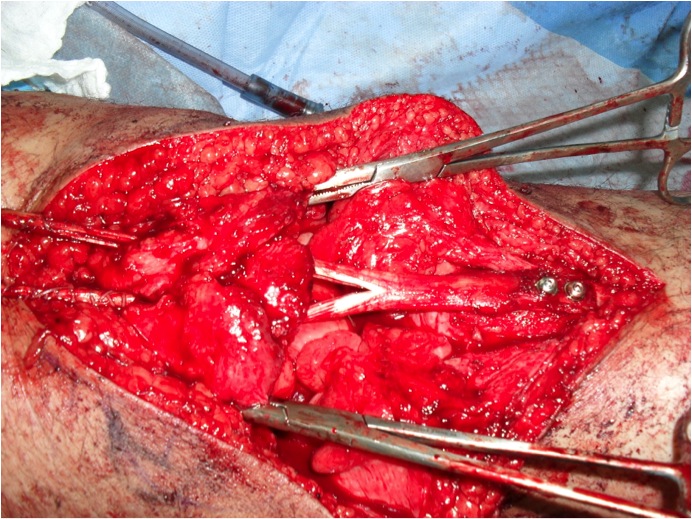

2. Avulsion from tibial tuberosity

Repair with suture anchors

3. Midtendon rupture

May need augmentation with hamstring tendon

Augmentation

1. Semitendinosus autograft

- leave semitendinosus attached distally

- pass through distal pole patella

- reattach to tibia on lateral side

2. Patella tendon Allograft

3. Lars Ligament

Chronic Rupture

Reconstruction

Case: Reconstruction with tendoachilles allograft, bone block in tibia

Case: Reconstruction with Hamstring Autograft (if patella relatively low) or Tibialis Posterior